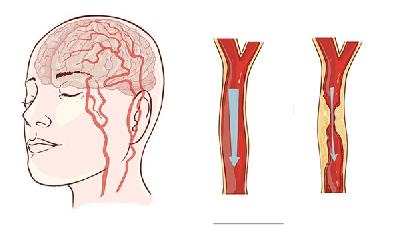

震颤型脑瘫多由锥体外系损伤及小脑损伤引起,其严重的影响着患者的身心健康,震颤型脑瘫是脑瘫常见类型之一,会导致震颤型脑瘫患者肌肉控制失调引起的身体运动困难和体位困难,严重的影响了患者的生活自理能力,所以震颤型脑瘫的治疗是非常有必要的。那么,男子震颤型脑瘫饮食方面需要注意什么呢?最近有越来越多的证据证实,饮食结构是震颤型脑瘫的一大重要因素。实验室研究结果显示,震...